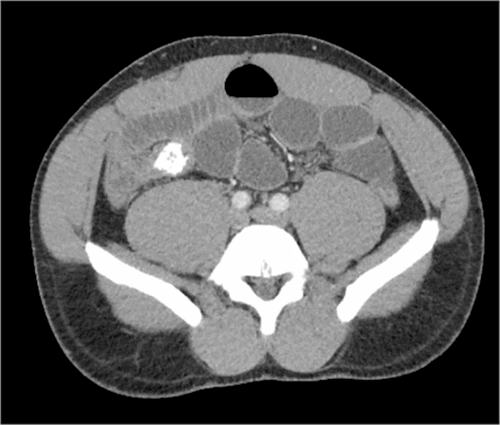

A 41-year-old previously healthy Libyan male presented with a two-day history of nausea, vomiting, and abdominal pain. He reported an inability to tolerate sips of water. He describes no changes in his diet and no strange or abnormal items being ingested before this episode. He had never experienced this type of pain or bloating before. He had a very firm, muscular abdomen with severe distention. He was diffusely tender but did not have signs of peritonitis. He was mildly tachycardic to 110 beats per minute. At this time, his laboratory evaluation showed acute kidney injury with creatinine elevation to 2.5 mg/dL and hypochloremic, hypokalemic metabolic alkalosis from repeated emesis. Given this clinical picture, a CT scan was obtained, which showed a high-grade mechanical obstruction in the distal ileum associated with a calcified density or mass (Figure 1). Additional calcified densities were identified more proximal in the small intestine located in the pelvis (Figure 2). Due to the high-grade obstruction and the calcified mass, surgical intervention was recommended. The patient was very hesitant initially but finally agreed to undergo exploratory laparotomy with possible small bowel resection.

Figure 1. Calcified Mass in Terminal Ileum. Published with Permission